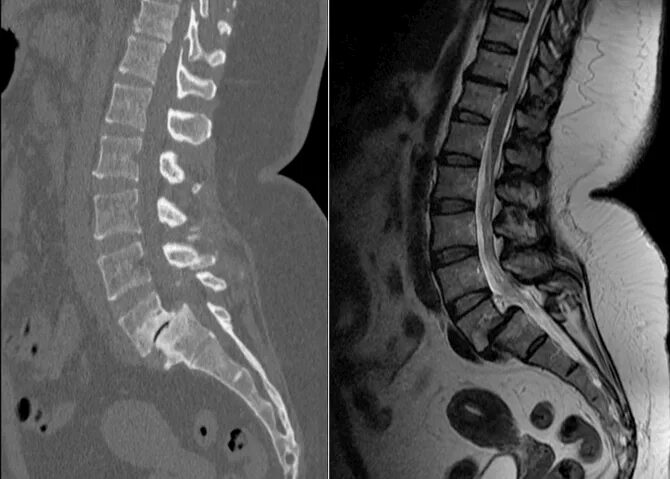

Смещение позвонков поясничного операция